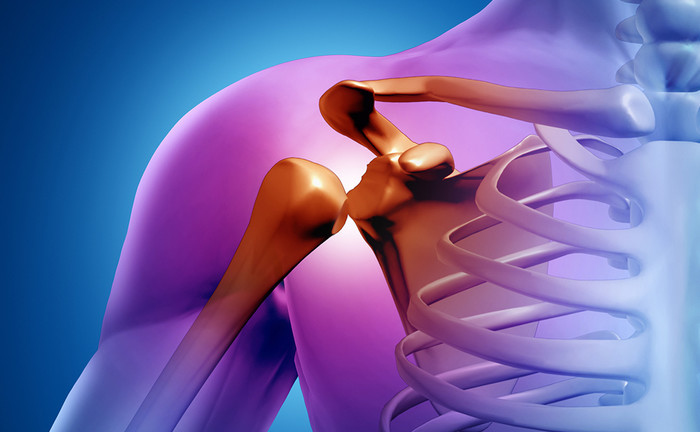

어깨뼈 골절은 예기치 않은 사고로 인해 발생하는 불행한 상황 중 하나입니다. 스포츠 활동 중, 교통사고, 또는 일상생활에서의 낙상 등 다양한 원인으로 인해 발생할 수 있는 이러한 부상은 대부분의 경우 치료 가능하지만, 통증 관리와 재활 과정이 매우 중요합니다. 이 글에서는 어깨뼈 골절의 초기 통증부터 시작하여, 수술 후 재활 치료까지의 과정을 자세히 살펴보며, 이를 통해 어깨 골절을 경험할 수 있는 사람들이 겪는 고충과 그 해결책에 대해 심도있게 탐구하고자 합니다. 또한, 어깨 골절의 치료 비용과 실비보험 적용 등 금전적인 측면도 함께 다루어, 독자 여러분이 이러한 상황에 대비할 수 있는 유용한 정보를 제공하고자 합니다.

어깨뼈 골절은 교통사고, 스포츠 활동 중 또는 낙상으로 인해 발생할 수 있습니다. 통증의 정도와 기간은 골절의 심각성, 위치, 치료 방법에 따라 다양하게 나타납니다. 초기에는 골절 부위의 부기와 충격으로 인한 극심한 통증이 나타날 수 있으며, 병원에서 제공하는 진통제는 이러한 통증을 상당히 완화시켜줍니다. 골절된 뼈가 안정되고 치유 과정이 진행됨에 따라 통증은 점차 감소하게 됩니다. 대부분의 경우, 골절 직후 몇 주 안에 통증은 크게 줄어들며, 이후 재활 과정에서 관리할 수 있는 수준으로 조절됩니다.